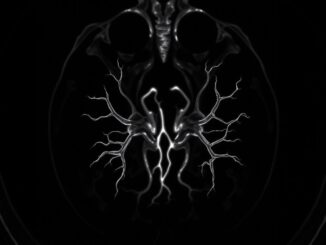

Новосибирские хирурги спасли девушку с синдромом Щелкунчика

Почечная вена пациентки оказалась сдавленной между аортой и отходящей от нее артерией. В Новосибирском национальном медицинском исследовательском центре имени Мешалкина хирурги провели успешную операцию по [читать далее …]